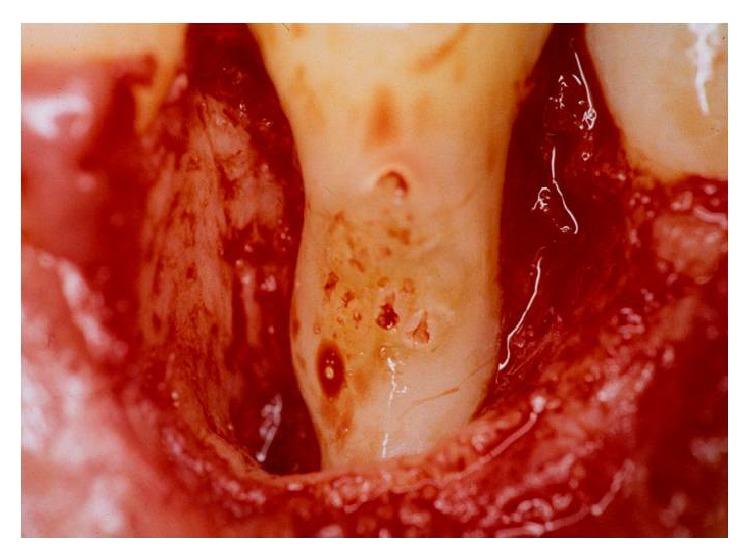

Dental anatomy is quite complex and diverse factors must be taken into account in its analysis. Teeth with anatomical variations present an increase in the rate of severity periodontal tissue destruction and therefore a higher risk of developing periodontal disease. In this context, this paper reviews the literature regarding enamel pearls and their implications in the development of severe localized periodontal disease as well as in the prognosis of periodontal therapy. Radiographic examination of a patient complaining of pain in the right side of the mandible revealed the presence of a radiopaque structure around the cervical region of lower right first premolar. Periodontal examination revealed extensive bone loss since probing depths ranged from 7.0 mm to 9.0 mm and additionally intense bleeding and suppuration. Surgical exploration detected the presence of an enamel pearl, which was removed. Assessment of the remaining supporting tissues led to the extraction of tooth 44. Local factors such as enamel pearls can lead to inadequate removal of the subgingival biofilm, thus favoring the establishment and progression of periodontal diseases.

牙齿解剖结构相当复杂,在分析时必须考虑多种不同因素。存在解剖变异的牙齿会使牙周组织破坏的严重程度增加,因此患牙周病的风险更高。在此背景下,本文回顾了有关釉珠及其在严重局限性牙周病发展以及牙周治疗预后方面影响的文献。对一名主诉下颌右侧疼痛的患者进行的影像学检查显示,右下第一前磨牙颈部区域周围存在一个不透射线的结构。牙周检查发现广泛的骨质流失,因为探诊深度在7.0毫米至9.0毫米之间,此外还有严重出血和化脓。手术探查发现存在一颗釉珠,并将其取出。对剩余支持组织的评估导致拔除了44号牙。诸如釉珠等局部因素会导致龈下生物膜清除不充分,从而有利于牙周病的形成和进展。